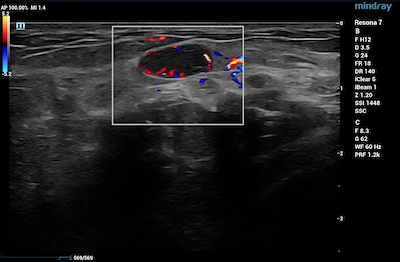

- Thyroid – CDI is routinely used in thyroid gland imaging to further classify and aid in diagnosing thyroid lesions.

Power Doppler Imaging of Thyroid Lesion